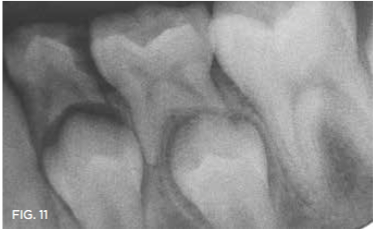

Case 2. This 2-year-old boy had mesial caries lesions of his maxillary central incisors associated with chronic plaque accumulation and lack of tooth brushing or flossing by the parents (Figure 5 and Figure 6). The parents, who were given extensive instructions to remedy the oral hygiene problem, consented to SDF application despite the black discoloration. They related that they not only wanted to avoid a repair appointment for the child, but they also liked the idea that traditional restoration could be delayed until he was older and could more easily tolerate treatment. Three months after initial SDF application, the solution was reapplied (Figure 7).

Fig 5. Mesial caries lesions in 2-year-old patient.

Fig 5